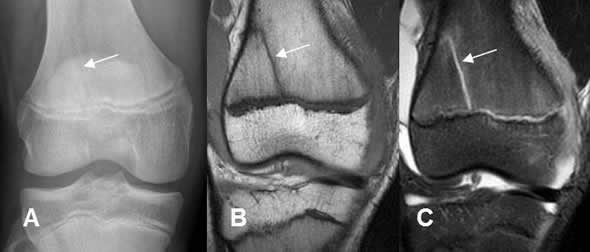

Fig 77. Salter tipo IV.

A: Rx AP y B: TAC reconstrucción sagital. Fracturas oblicuas con compromiso de las epífisis y metáfisis del tobillo y la rodilla.